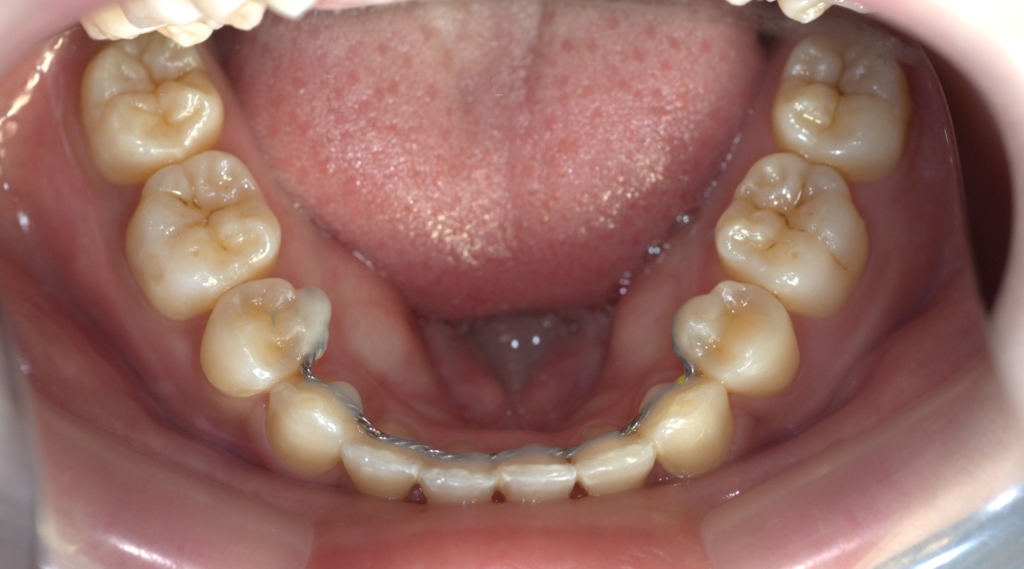

【After】

矯正後の状態をレントゲン写真で確認すると、

【保定】 上下ともフィックスタイプ&クリアリテーナー